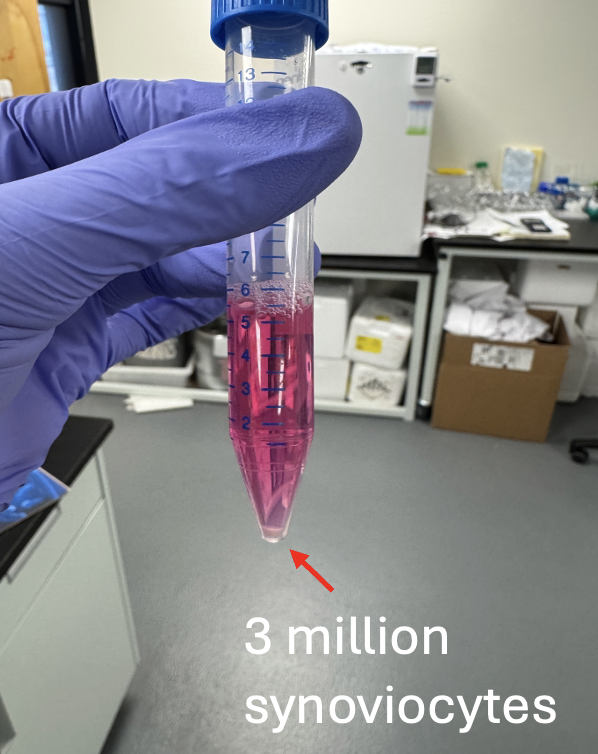

Masters work - validation of rotator cuff repair patch with stem cell implanted hydrogel.

Implanting cells into hydrogel and performing live/dead stain assay.